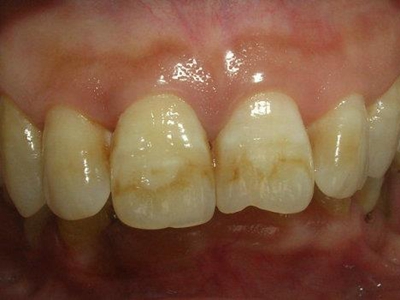

牙齿

条纹

牙釉质发育不全牙齿有条纹凹陷图

牙釉质发育不全患者牙齿上出现棕褐色的条纹凹陷,部分融合成一小片,牙齿整体发白,形态较完整,患者无明显疼痛、流血等异常表现。